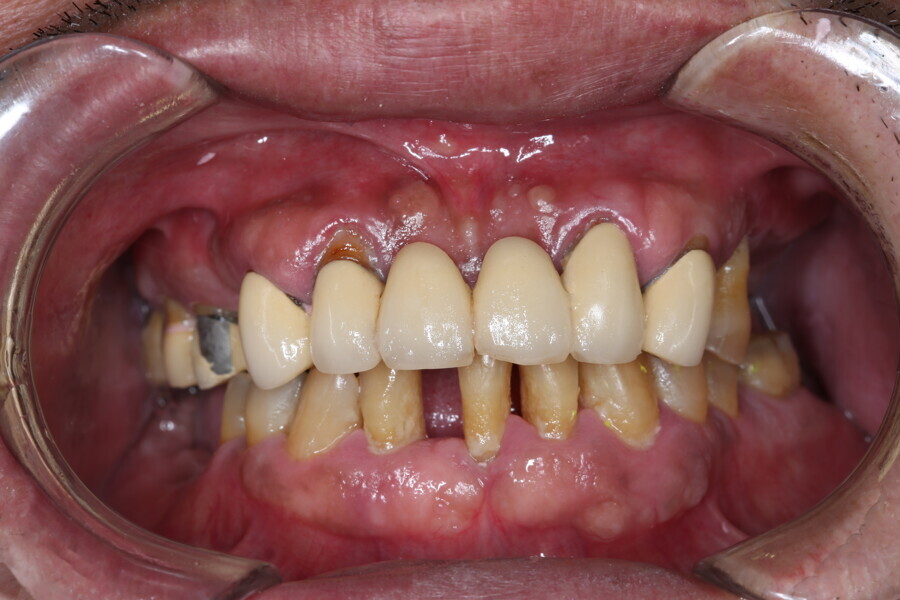

Compromised maxillary dentition treated with Straumann Pro Arch and a digital workflow